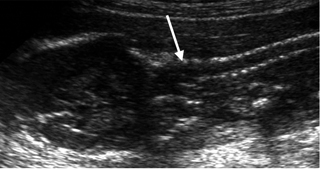

Εικόνα 5. Επιμήκης τομή ΣΣ από το ινίο έως τον κόκκυγα όπου συγκλίνει, με το δέρμα να την καλύπτει χωρίς ασυνέχειες σε ολόκληρο το μήκος της. Διακρίνονται τα φυσιολογικά κυρτώματα ΘΜΣΣ/ΟΜΣΣ. Εικόνα 6. Στεφανιαία τομή στο ύψος της ΑΜΣΣ και του ινίου. Παράλληλα οστικά εντυπώματα, χωρίς ασυνέχειες. Αποκλεισμός μηνιγγομυελοκήλης (βέλος). Εικόνα 7. Εγκάρσια τομή ΘΜΣΣ. Εμφανής οι τρεις πυρήνες οστέωση (βέλη) και μία πλευρά.